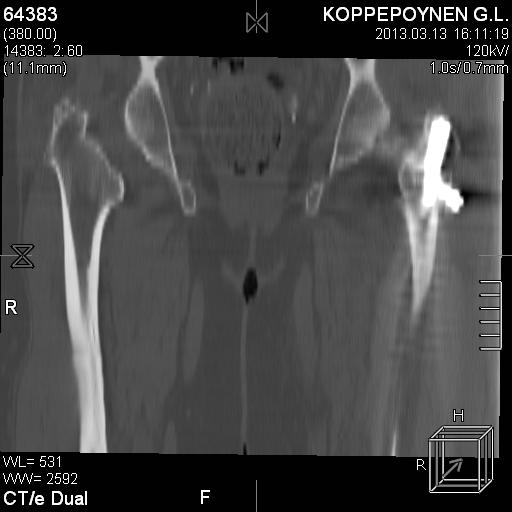

Делали КТ после операции.

Непонятно, на какой вопрос с помощью КТ хотели получить ответ? IMHO это было ненужное исследование, все проблемы были видны на обычном снимке. А что на второй проекции? Где аксиальная или профиль?